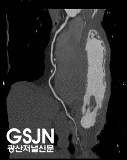

64 ä³Î Volume CT´Â ¸ÞÆ®¸¯½º ÇüÅÂÀÇ 64°³ÀÇ °ËÃâ±â¸¦ ¼³Ä¡ÇÏ¿© 0.625mmÀÇ °¡Àå ¾ãÀº °£°ÝÀ¸·Î 1ÃÊ¿¡ ¾à 200°³ÀÇ ´Ü¸éÀ» ÃÔ¿µÇÒ ¼ö ÀÖ½À´Ï´Ù.

°í¼ÓÃÔ¿µ°ú ¸¹Àº ´Ü¸éÀÇ °Ë»ç·Î ȯÀÚÀÇ ÇØºÎÇÐÀû Á¤º¸°¡ ÈξÀ ¸¹¾ÆÁ³À¸¸ç ¿µ»óÀÇ ÁúÀÌ ÁÁ¾ÆÁö°í 3Â÷¿ø ¿µ»óÀ¸·Î À籸¼ºÇϱ⵵ ½¬¿öÁ³½À´Ï´Ù. ÀÌ·Î½á ±âÁ¸ CTÀÇ 2Â÷¿ø ¿µ»ó¿¡¼­´Â º¼ ¼ö ¾ø¾ú´ø ºÎºÐÀ» ´õ ÀÚ¼¼ÇÏ°Ô È®ÀÎÇÒ ¼ö ÀÖ°Ô µÇ¾î º¸´Ù Á¤È®ÇÑ Áø´ÜÀÌ °¡´ÉÇØ Á³½À´Ï´Ù.